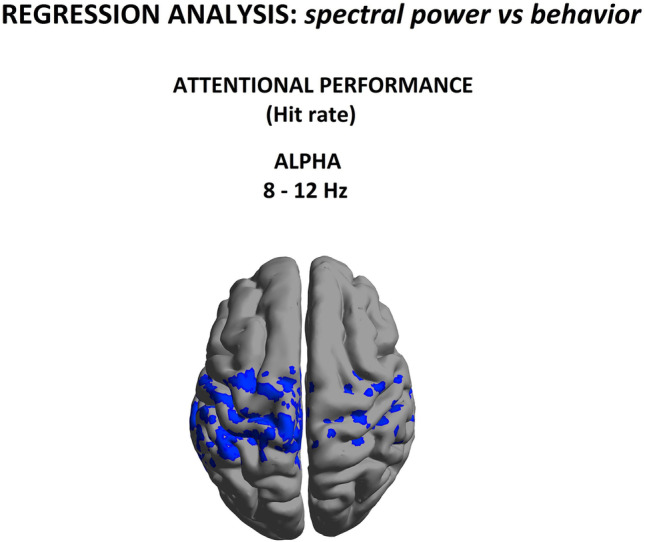

Brain-behavioral correlates

There were no statistical differences in either commission errors (p > 0.05) or hit rate (p > 0.05) between CUD patients and controls, indicating that inhibitory control and sustained attention were similar between the two groups.

Our group-level analyses indicated anomalous spectral power pattern between patients and control subjects; however, they cannot be used to directly infer any potential links with attentional performance. To disentangle neurobehaviorally specific from nonspecific EEG power in CUD patients, we conducted regression analyses directly testing for any relationships between individual patients’ relative alpha source power and their attentional performance, as indexed by the Hit score (success rate) in the Go/NoGo task. As seen in Fig. 4, a significant negative correlation (t = −2.40, p < 0.05) with attentional performance indicates that decrease Hit rate accuracy was predicted by increases in alpha power within a homologous set of nodes in somatosensory and motor Brodmann areas. This is consistent with the literature linking attention with frontal activity in healthy subjects (Mazaheri et al., ref. 2009), and reinforces the idea that the changes in alpha-band may be specifically related to difficulties in spatially directed attentional processing in CUD.

Conjunction analysis between group spectral power abnormalities and correlates of behavioral deficits

Finally, as shown in Fig. 5, we investigated whether abnormal spectral power seen at the group level was consistent with changes associated with interindividual differences in attentional performance. In other words, was there evidence for a selective disruption of alpha rhythm in cannabis addiction that impacted attentional function? Consequently, we performed a conjunction of tests (i.e., global null hypothesis) to identify the overlap, if any, between the statistically-significant (p < 0.05) group-level relative alpha power differences (Fig. 2) and the regression between relative alpha power and omission errors (Fig. 4).

Interestingly, we identified a statistically reliable overlap within alpha band and attentional performance in the left sensorimotor and temporal regions (Brodmann area 4, 6, 20 with maximum (t = 1.50, p < 0.05)).